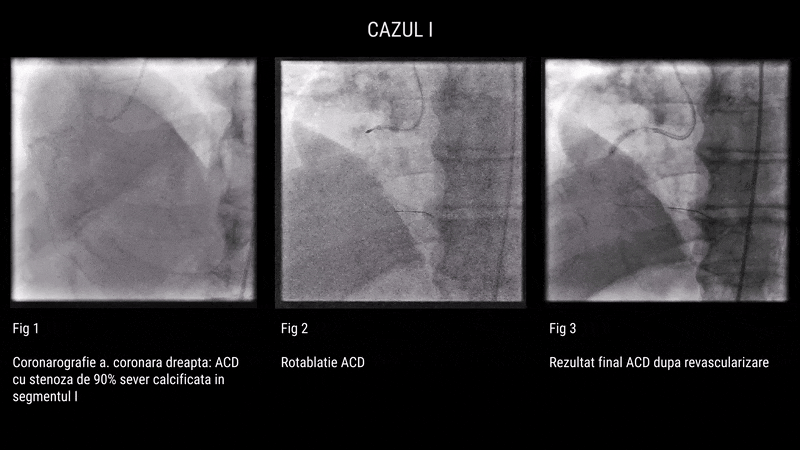

Primul pacient, în vârstă de 63 de ani, cu multiple comorbidități (HTA grad III, diabet zaharat tip 2, dislipidemie, insuficiență cardiacă clasa II–III NYHA), a fost diagnosticat cu leziuni tricoronariene severe. Coronarografia a evidențiat stenoze seriate de 90% pe LAD, leziuni de 80–90% pe MG1 și ACD, precum și calcificări importante. Intervenția a inclus rotablație și angioplastie cu implantare de 7 stenturi, cu rezultat angiografic final favorabil.